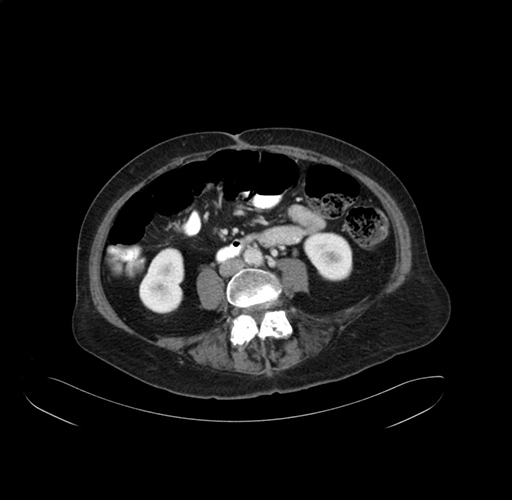

Pre-Chemo: Axial Venous

Axial Venous